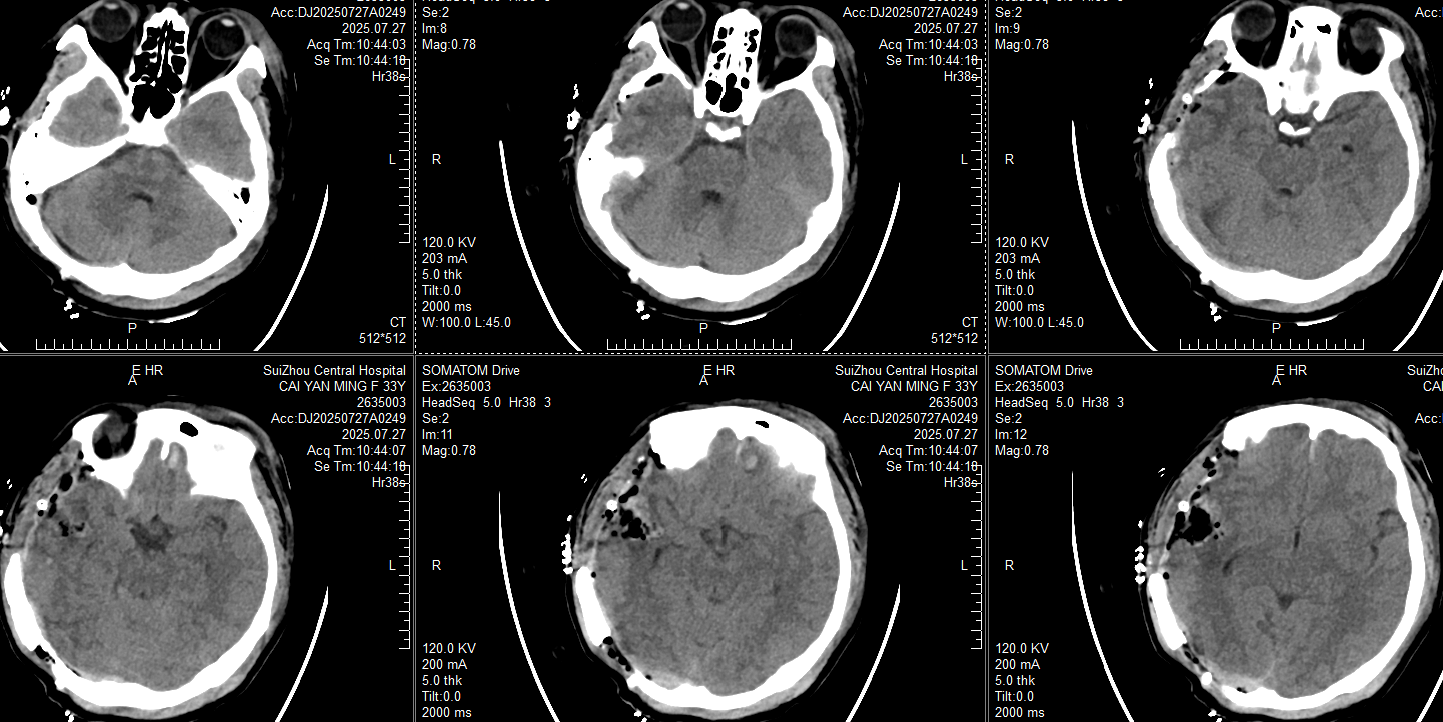

入住ICU后镇痛镇静、气管插管,止血、抑酸、预防癫痫、抗炎对症治疗;21:33复查CT:

此时患者瞳孔等大同圆直径约2mm,对光反射均存在,颞叶血肿未完全形成,在和家属交代开颅手术方案:右侧枕部开颅清除硬膜外血肿去骨瓣减压,后再复查CT对比右侧颞叶出血进展情况。家属还在考虑手术方案时,23:20患者右侧瞳孔开始放大,立即复查CT: